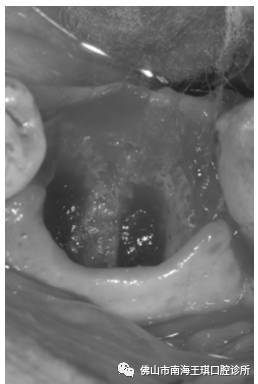

看上去挺好的一个牙齿,中间有一个小洞,洞里还有一个棉花。一拿出那个棉花,全诊室都弥漫上了那种难以言说的恶臭味儿。不用说,是颗难搞的牙了。

片子显示底穿了,牙槽骨也吸收很多了。根尖周围也有阴影的。

龋洞是细菌的温床。一个长年累月没有封住的洞,更加滋生了很多细菌,把髓底都“吃”穿了,并且,整个牙体,也完全成了个空壳。只能拔掉种牙了。